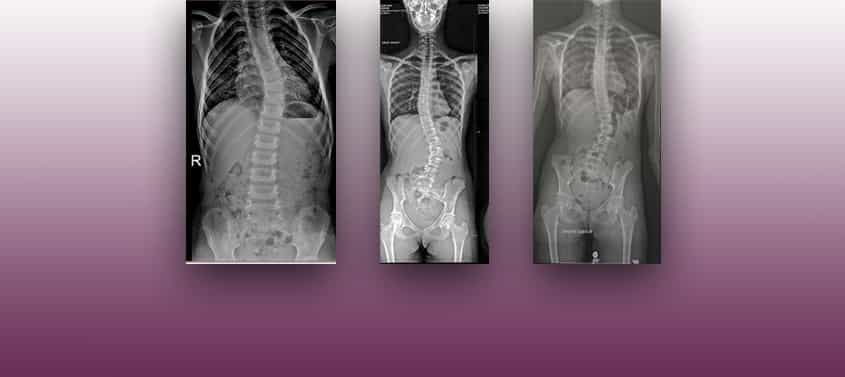

Skoliose

Letzte Überarbeitung: 6/3/2026, Dr. med. Miguel B. Royo Salvador, Arztnummer: 10389. Neurochirurg und Neurologe. Definition Die idiopathische Skoliose besteht aus einer seitlichen Abweichung der Wirbelsäule unbekannter Ursache, die bei Frauen öfter vorkommt und häufiger im Wachstumsalter beobachtet wird. Abbildung 5. – Magnetresonanztomographie (MRT) mit Frontalschnitt der Wirbelsäule bei einer idiopathischen Skoliose, bei der der Spinalkanal […]